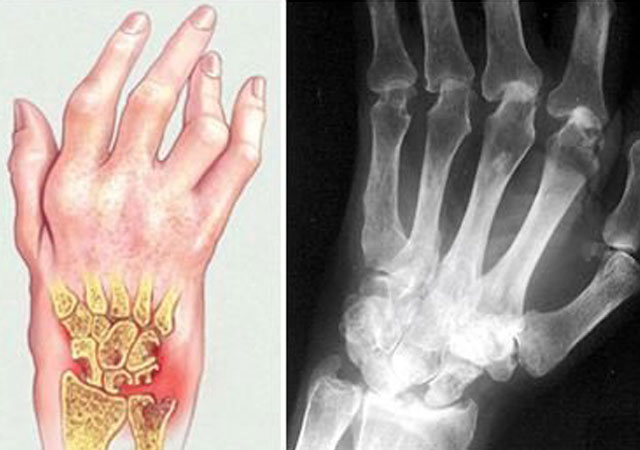

成都风湿病专科医院风湿关节炎首先要去医院,通过抽血化验能确诊。如果确诊是风湿性关节炎,要通过药物来控制炎症。控制炎症可能需要很多种药物,也可以通过对关节的局部治疗,然后吃了这些药物,还要再抽血来确认炎症控制怎么样。如果炎症控制的不好,久而久之关节会恶化、会变形,较终到较后需要手术才能够治好它。

关节炎症